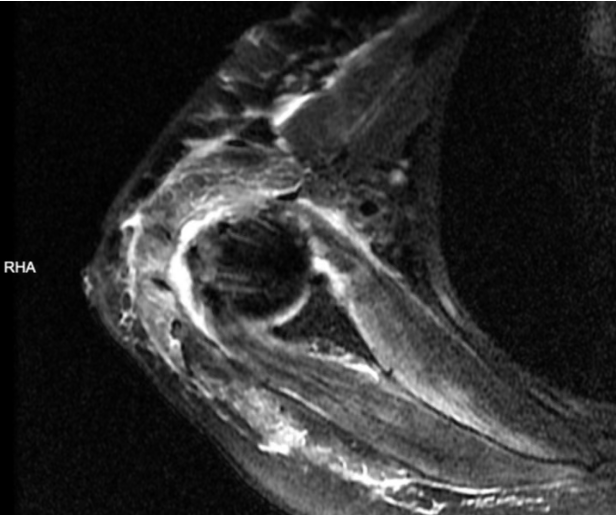

▲肩胛下肌撕裂。

通过磁共振检查和查体,我们判断该患者存在冈上肌腱、冈下肌腱、肩胛下肌腱等三条肌腱的撕裂,而且冈上肌腱的断端已经回缩至肩胛盂水平,大结节结及肱骨头裸露,属于巨大的不可修复的肩袖撕裂。